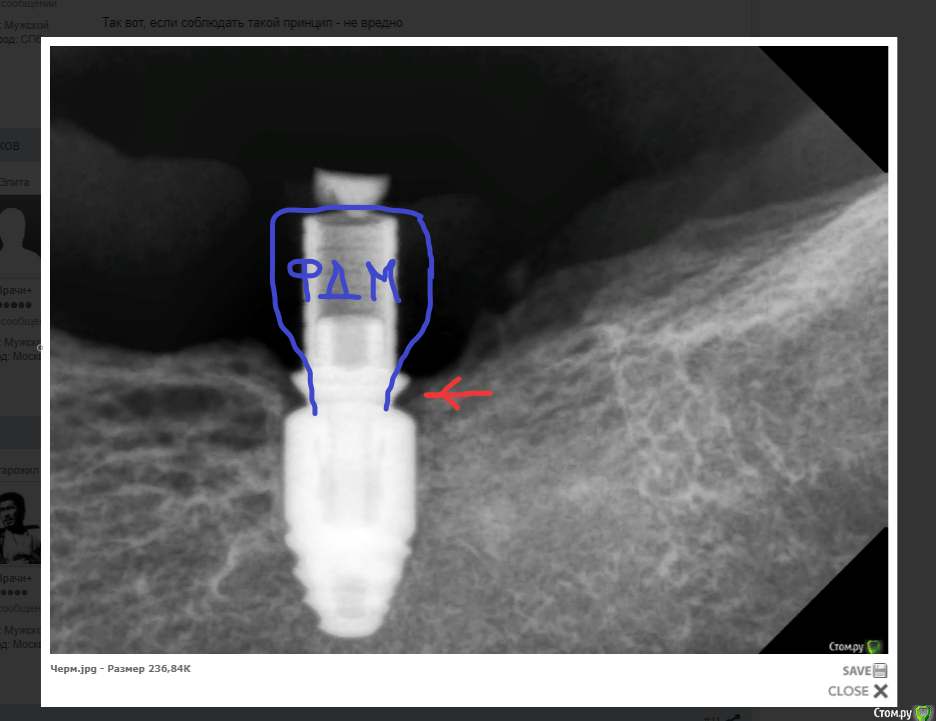

Irouil Опубликовано 18 декабря, 2020 Поделиться Опубликовано 18 декабря, 2020 (изменено) Мне кажется, это вредно. Заблуждение? Я там описАлся в предыдущем посте, конечно же речь идёт об эпителиальном этаже, а соединииельно-тканный наоборот - не трогайте. Извините Так вот, если соблюдать такой принцип - не вредно Изменено 18 декабря, 2020 пользователем Irouil Ссылка на комментарий

колесников Опубликовано 18 декабря, 2020 Поделиться Опубликовано 18 декабря, 2020 Вредно ишемию делать и оставлять . Я под анестезией никогда не меняю фдм,не заметишь,пропустишь-все испортишь. Ставлю сразу финальный диаметр,высота разная может быть. Подсекать в основании не плохо . То что была боль при замене фдм-первый звоночек,видимо десневая шахта глубокая и стенки не стабильны,не имеют костной поддержки. Но есть свой плюс-можно впихнуть широкое основание,хотя я против такого профиля. Уступ высотой 1 мм портит всю работу,не сейчас,так позднее. 1 Ссылка на комментарий